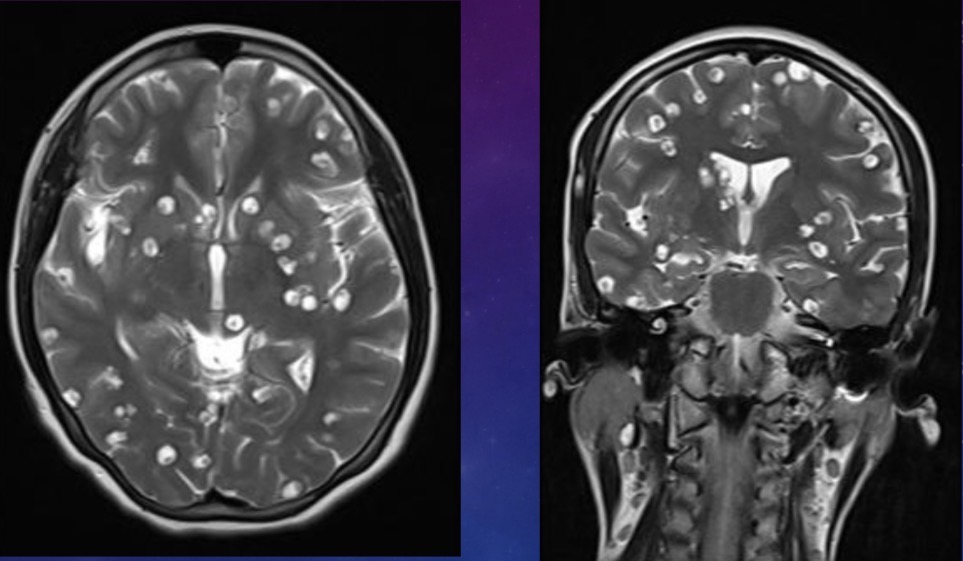

20 year-old female presents with convulsions

Neurocysticercosis - vesicular stage